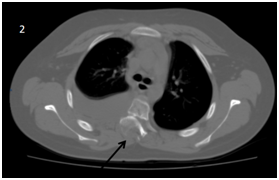

Two days after the in initial emergency room visit, the patient is admitted again with respiratory distress, fever and decreased oximetry by 88%. Because of the acute symptoms and clinical examination, pneumonia is suspected. IV antibiotic its initiated. Because previous the X-ray showed no other data, a computed tomography was performed, and pleural effusion was  confirmed with T4 listhesis (Figures 2-4).

<strong>Figure 4 </strong> Thorax CT scan coronal view. Right pleural effusion and absence of 5, 6 and 7 right costal arcs.

Figure 4 Thorax CT scan coronal view. Right pleural effusion and absence of 5, 6 and 7 right costal arcs.